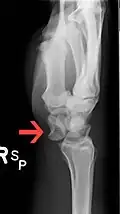

Perilunar dislocation as seen on x-ray.

The lunate bone is the most frequently dislocated carpal bone.